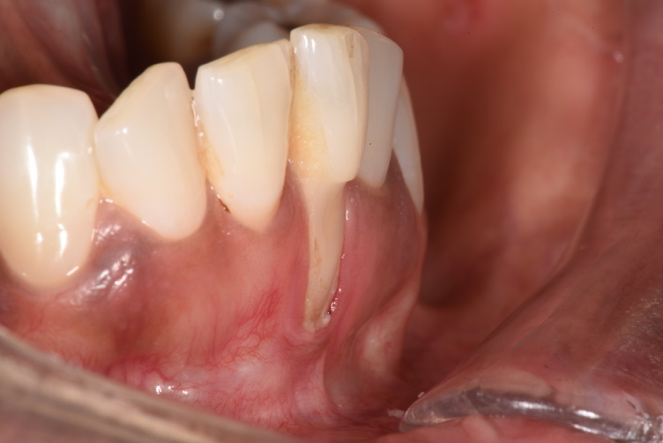

An example of a lower front tooth suffering from severe gum recession. Note the accumulation of plaque on the root. Nearly the entire root has been exposed.